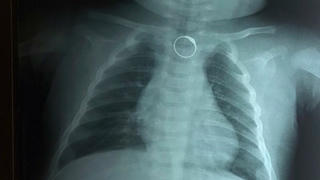

từ khóa: #nuốt nhẫn